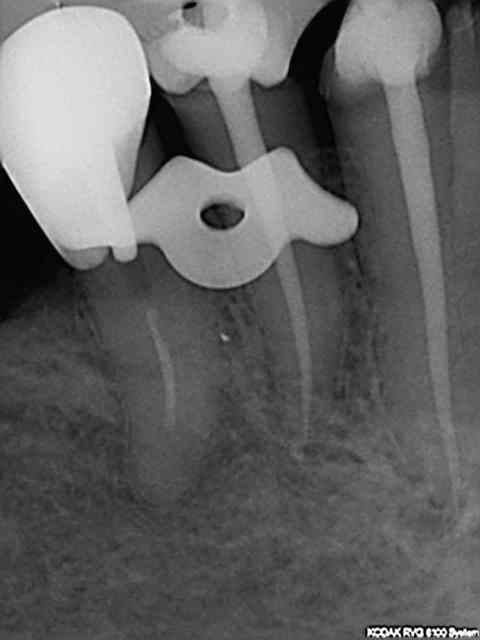

J'ai fait une reprise de TR sur 27 en novembre dernier ; digue, javel, NiTi, pour un bon résultat radio.

Si-si il a raison les radios exposées en nombre font toutes preuve d'un traitement parfait et ce en un temps plus que raisonnable.

A partir de là tous les instruments d'endo sont au préalable en place sur un instrument rotatif. Sx protaper sur l'entran, largo numéro 3 sur double bague verte, s1 protaper sur endomaster, r25 réciproc sur wd silver, SAF (pas tout le temps vu les 50 euros de l'instrument jetable) Endo activator ou rinsendo plutôt ngap oblige !)

Je fais la recherche des canaux avec l'entran et le sx que j'essaye de faire progresser le plus possible en direction apicale (sans forcer comme un bourrin, hein !) puis ouverture au largo de l'entrée canalaire et re-sx pour progresser encore jusquà environ entre 15 et 20 mm de lt (dépend de la longueur estimée de la racine à la radio pré op et de sa perméabilité). Ensuite passage du s1 avec l'endomaster qui en général descend à la lt sans problème (réglage de l'endomaster à -0.5mm lt).Stop sur le r25 qui descend sans problème à la lt. Irrigation tout au long de la procédure évidemment (sauf s1 car la lt ne peut pas etre déterminée avec l'endomaster si trop de dakin). Récapitulation si problème à l'une des étapes mais c'est rare.